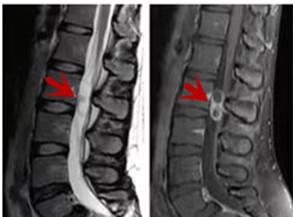

利器三:MRI(核磁共振)

MRI利于磁場(chǎng)和射頻脈沖使體內(nèi)的氫原子核發(fā)生磁共振現(xiàn)象而產(chǎn)生的圖像,對(duì)軟組織的分辨率很高,對(duì)于脊髓、椎間盤(pán)、神經(jīng)、血管、韌帶、骨髓、腰部肌肉及周?chē)浗M織有很好的顯示效果,可以清晰的顯示腰椎間盤(pán)突出對(duì)硬膜囊、神經(jīng)根壓迫程度,以及骨折是陳舊還是新鮮,同時(shí)在脊髓病變(如脊髓損傷、髓內(nèi)出血或腫瘤)、椎管內(nèi)膿腫/血腫、椎旁肌肉軟組織病變等方面也具有優(yōu)勢(shì),但是檢查時(shí)間較長(zhǎng),部分患者可能因體內(nèi)金屬植入物(如心臟起搏器、人工耳蝸等)而無(wú)法進(jìn)行檢查。

箭頭提示腰椎管內(nèi)腫瘤

紅色箭頭提示新鮮骨折,黃色箭頭提示陳舊性骨折